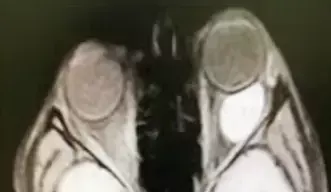

Рисунок 6. МРТ глазных орбит с контрастированием. На фоне проводимой терапии состояние без динамики, в связи с чем проведено дообследование: КТ орбит и МРТ орбит с контрастом. КТ показало образование левой орбиты, активно накапливающее контрастное вещество. МРТ орбит с контрастом — образование левой орбиты 2,6×1,5×2,9 см, активно накапливающее парамагнетик (см. рис. 6).